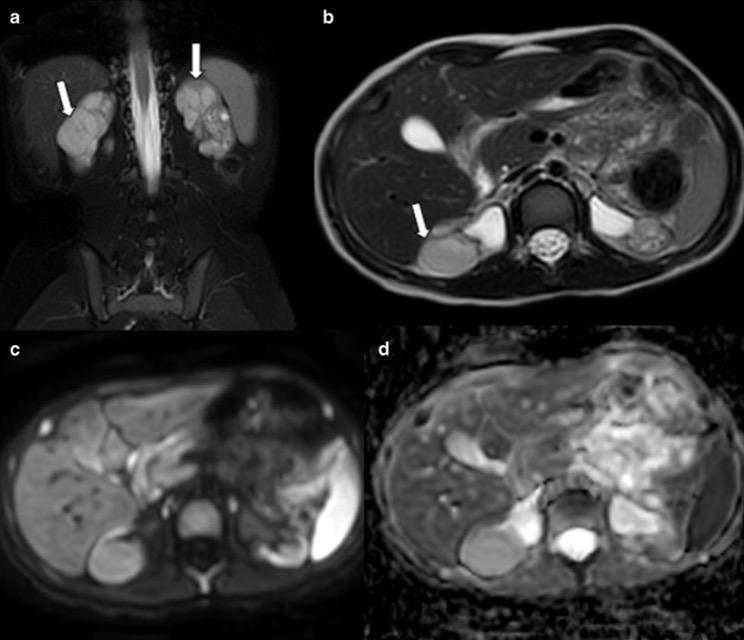

3. Pseudotumeurs rénales vasculaires

- Malformation artérioveineuse rénale

- Hématome sous-capsulaire spontané